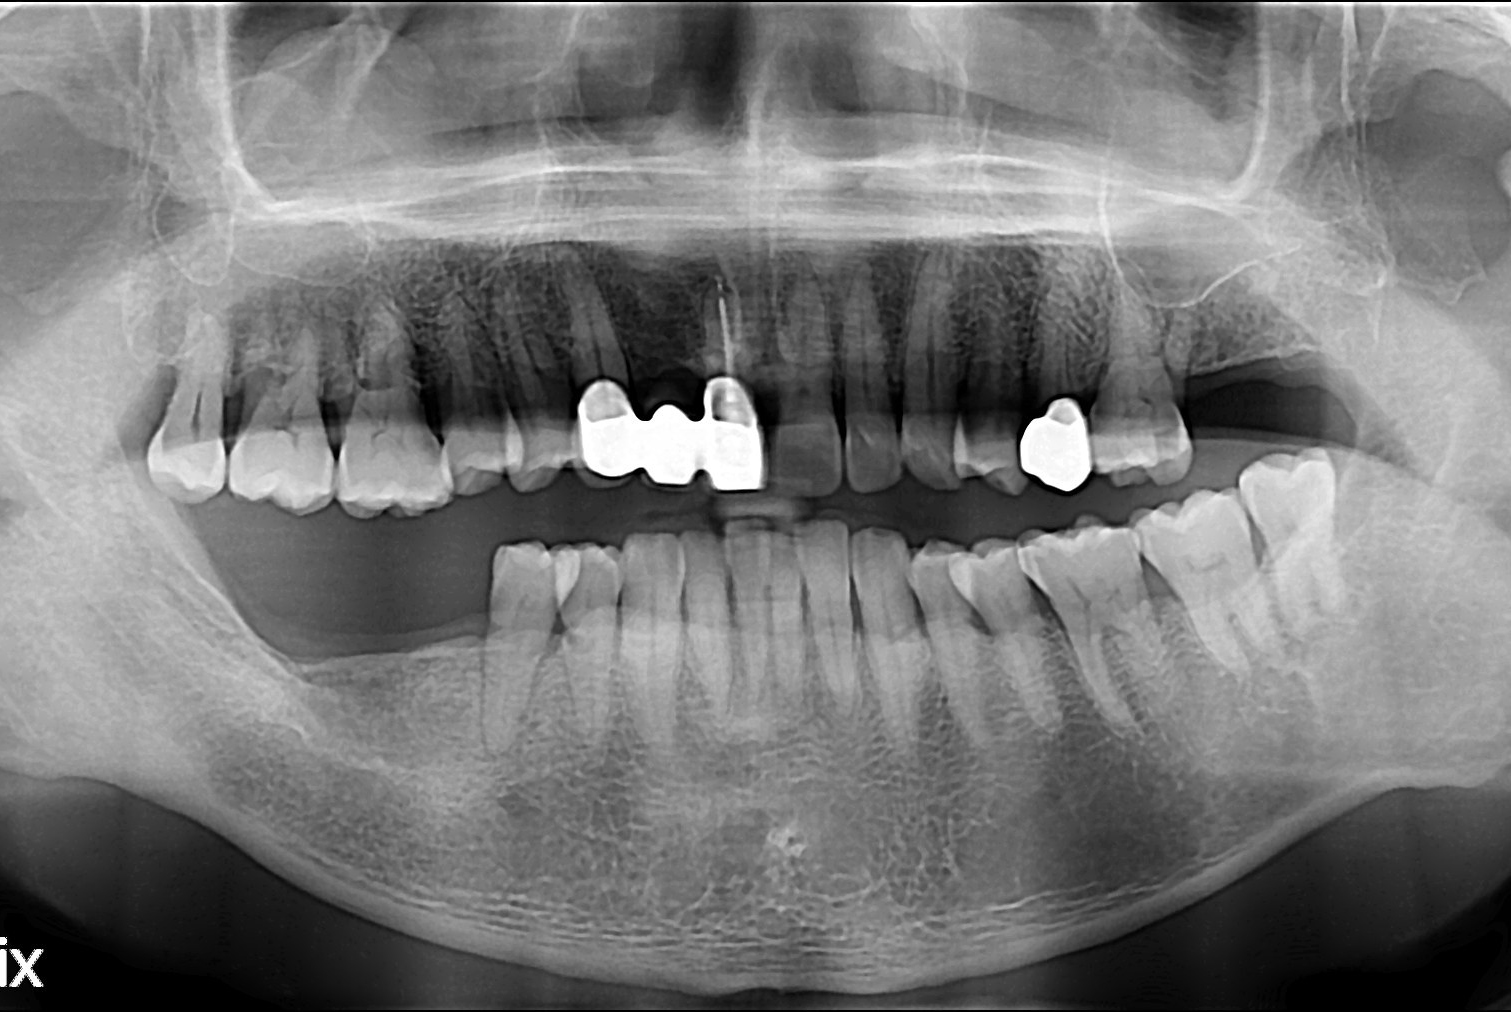

[임플란트] 임플란트

치료전 : 2018-03-14

세종치과는 많은 환자와 다양한 케이스를 바탕으로 항상 편안한 임플란트 수술을 제공하고자 노력하고,

오래동안 튼튼히 쓸 수 있는 임플란트 수술을 가장 큰 목표로 삼고 있습니다